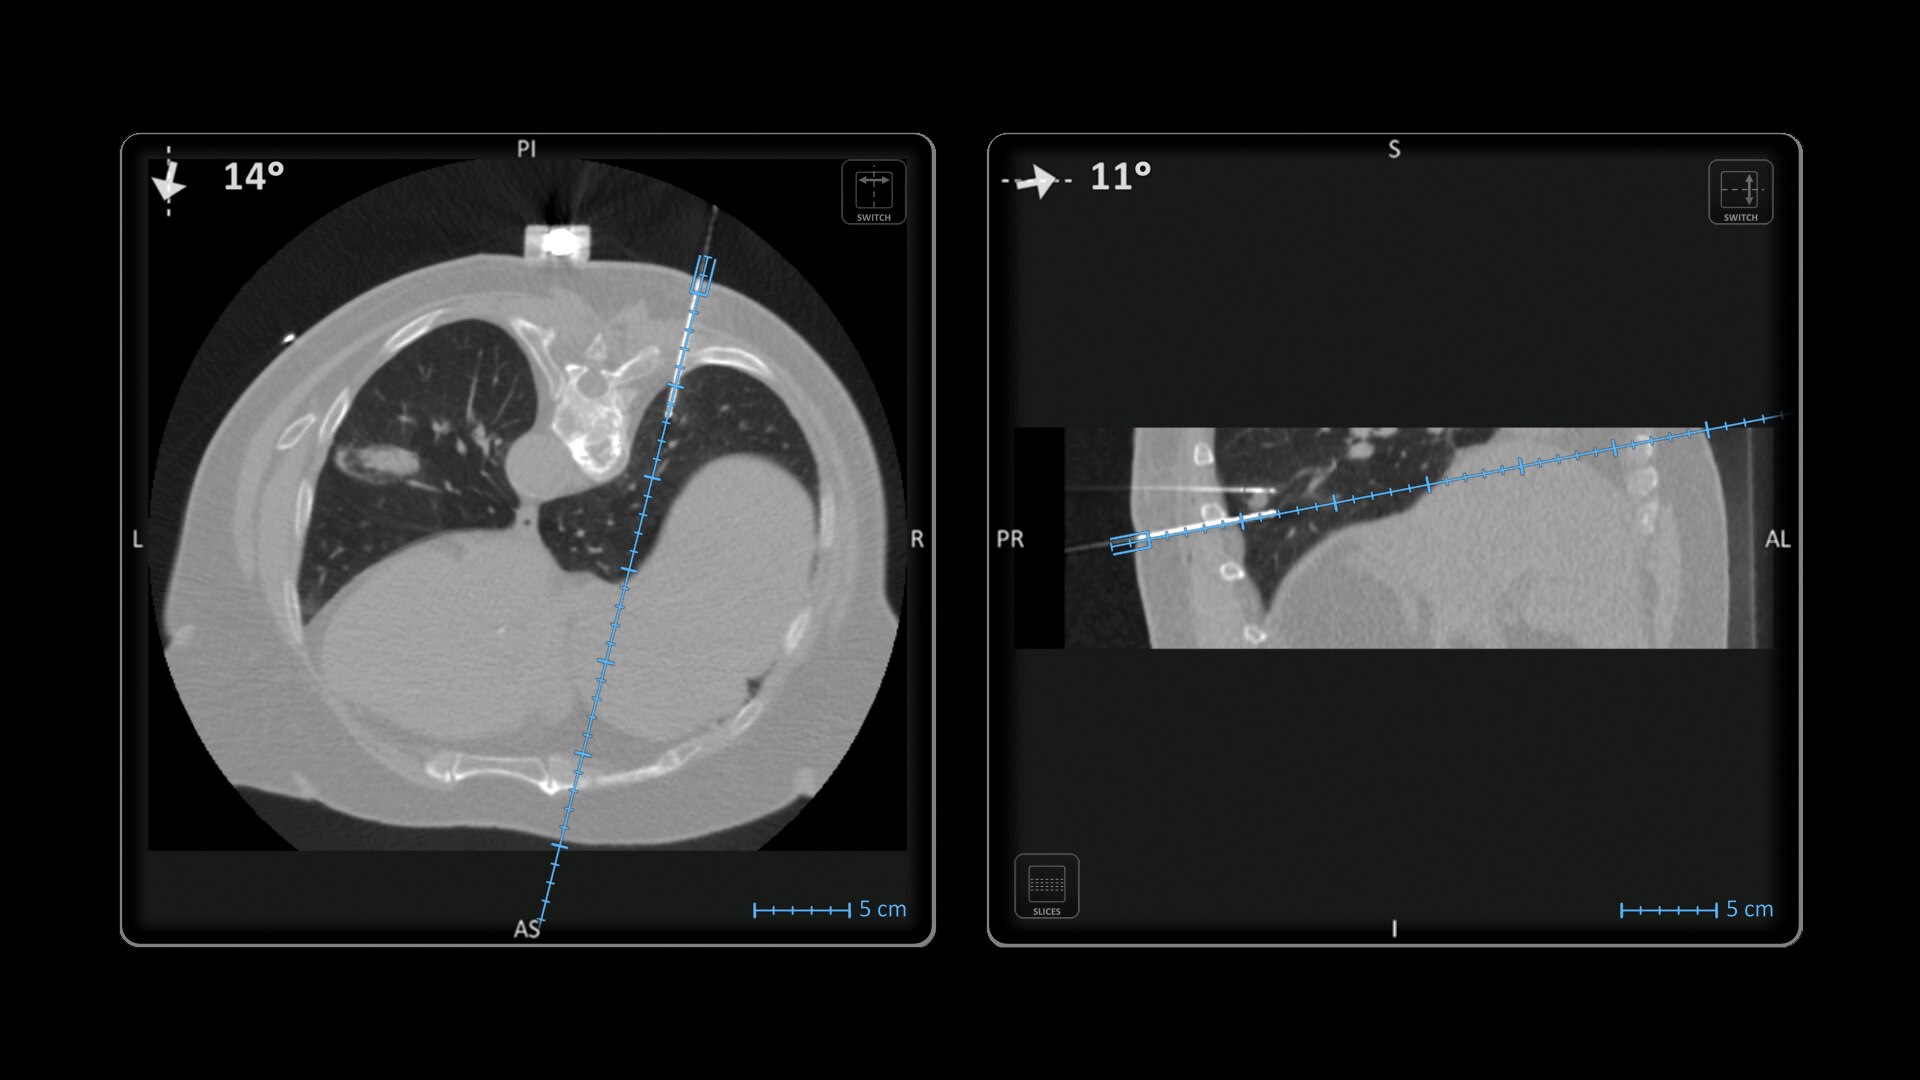

Imactis® CT-Navigation™ is an electromagnetic (EM) navigation solution for CT-guided percutaneous procedures

Imactis® CT-Navigation™ is designed to radically improve efficiency of Interventional procedures for clinicians and hospitals by increasing their accuracy.